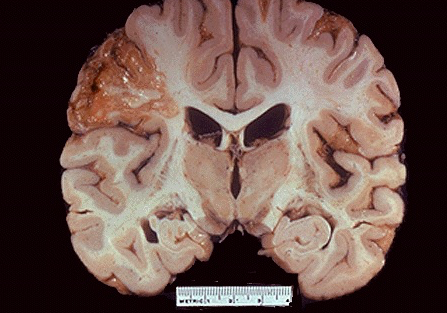

What type of infarct typically occurs in the brain?